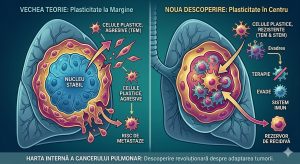

Plasticitatea celulară reprezintă capacitatea tumorii de a se adapta la condiții nefavorabile, inclusiv la chimioterapie sau atacul sistemului imunitar. Până de curând, consensul științific susținea că celulele cele mai periculoase, capabile să migreze și să formeze metastaze, se grupează la marginea tumorii pentru a „invada” țesuturile vecine.

„Am constatat că Tranziția Epitelio-Mezenchimală (TEM) — procesul care oferă celulelor trăsături agresive — este cel mai pronunțat în centrul tumorii, nu la marginea acesteia”, explică Anna Hozainova, cercetător în cadrul laboratorului de Biologie a Progresiei Tumorale.

Această descoperire explică, parțial, de ce multe terapii actuale eșuează. Celulele din centrul tumorii devin un rezervor de rezistență, capabile să evite supravegherea imună și să supraviețuiască tratamentelor agresive.

Mai mult, studiul subliniază că această plasticitate nu este uniformă, ci depinde în mod critic de profilul genetic al fiecărui pacient în parte. Această variabilitate face ca o abordare „universală” în tratamentul cancerului pulmonar să fie adesea ineficientă.